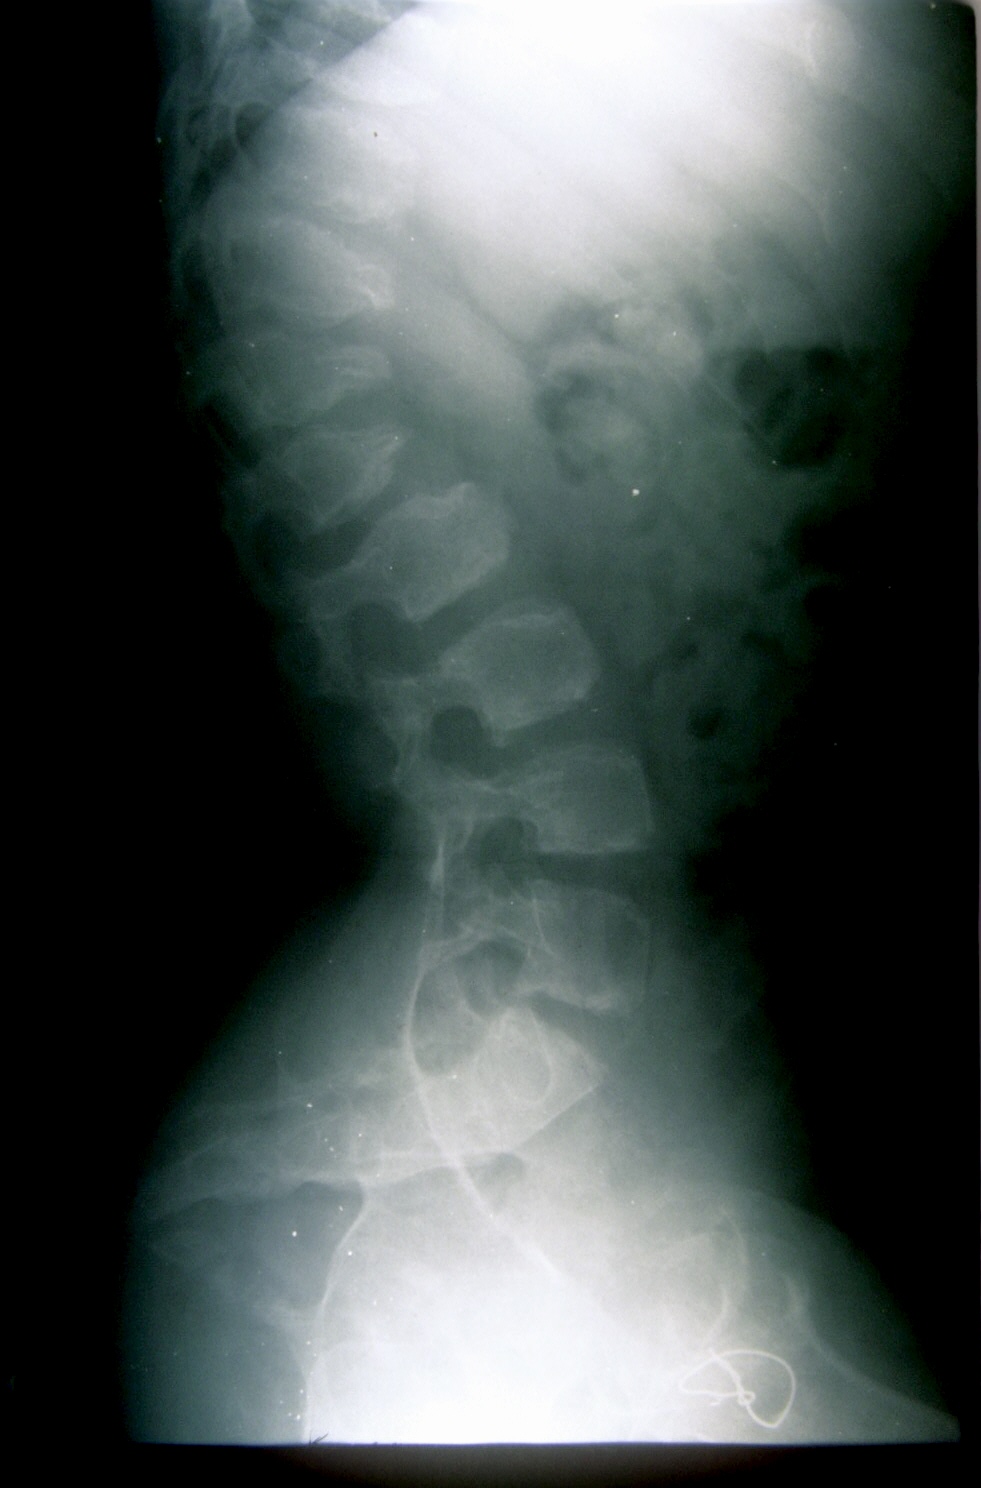

Seudoacondroplasia. [Pseudoachondroplasia]

2. Beals RB, Horton W. Skeletal dysplasias: an approach to diagnosis. J Am Acad Orthop Surg 1995;3:174-1.

3. Herring JA. Tchadjian´s. Pediatric Orthopedic, 3rd ed. Philadelphia: Saunder; 2002:1523-5.